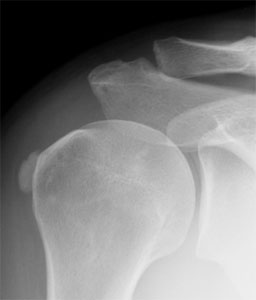

La tendinopatia consiste in un deposito di calcio in uno dei tendini della spalla che può verificarsi per due motivi:

a) le cellule tendinee si trasformano in cellule produttrici di calcio per un processo che si chiama “metaplasia” (tendinopatia calcifica); in questo caso il deposito di calcio si trova nel contesto del tendine.

b) il tessuto tendineo degenera a causa dell’invecchiamento e dell’usura, e successivamente calcifica (calcificazione degenerativa); invece qui il deposito è posto in corrispondenza dell’inserzione del tendine sull’omero.

La tendinopatia calcifica della spalla è una patologia ad eziologia sconosciuta che interessa principalmente soggetti con età compresa fra i 40 e i 50 anni, prevalentemente di sesso femminile ed è caratterizzata da formazione di depositi di calcio sui tendini della cuffia dei rotatori.